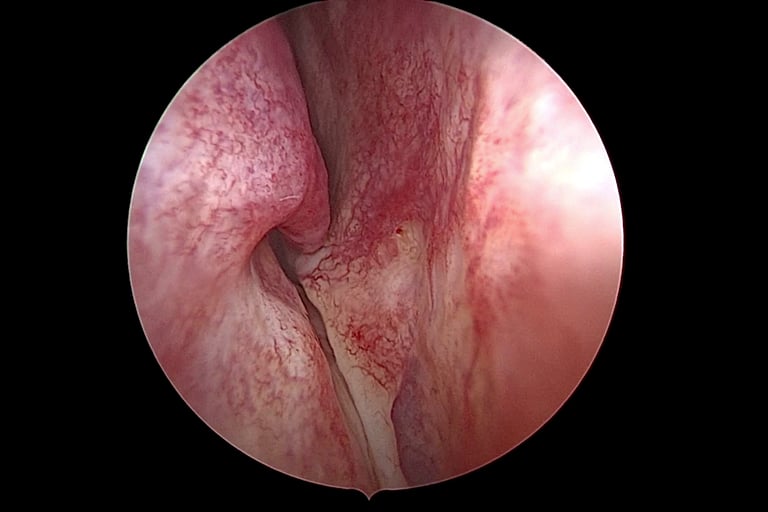

Endoskopski pregled nosa

Endoskopski pregled omogućuje liječniku detaljan uvid u unutrašnjost nosa pomoću tankog endoskopa s kamerom. Ovaj pregled pruža preciznu sliku anatomije nosa, uključujući:

Nosnu pregradu (septum) i moguće devijacije.

Prisutnost polipa, zadebljanja sluznice ili drugih anomalija.

Suženja nosnih kanala koja mogu otežavati disanje.

Endoskopija je ključna za otkrivanje strukturalnih problema koji mogu zahtijevati kiruršku korekciju.